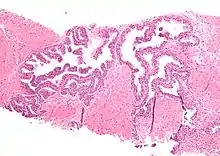

| Micrograph showing high-grade prostatic intraepithelial neoplasia. H&E stain. | |

High-grade prostatic intraepithelial neoplasia (HGPIN) is an abnormality of prostatic glands and believed to precede the development of prostate adenocarcinoma (the most common form of prostate cancer).[1][2]

It may be referred to simply as prostatic intraepithelial neoplasia (PIN). It is considered to be a pre-malignancy, or carcinoma in situ, of the prostatic glands.

Microscopically, PIN is a collection of irregular, atypical epithelial cells. The architecture of the glands and ducts remains normal. The epithelial cells proliferate and crowding results in a pseudo-multilayer appearance. They remain fully contained within a prostate acinus (the berry-shaped termination of a gland, where the secretion is produced) or duct. The latter can be demonstrated with special staining techniques (immunohistochemistry for cytokeratins) to identify the basal cells forming the supporting layer of the acinus. In prostate cancer, the abnormal cells spread beyond the boundaries of the acinus and form clusters without basal cells. In HGPIN, the basal cell layer is disrupted but present. PIN is primarily found in the peripheral zone of the prostate (75-80%), rarely in the transition zone (10-15%) and very rarely in the central zone (5%), a distribution that parallels the zonal distribution for prostate carcinoma.[7]